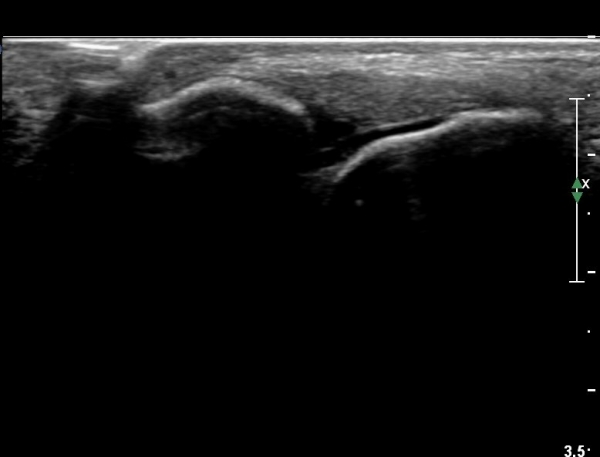

Á¾°ñºñ°ñÀδë Á¾´Ü¸é°Ë»ç¿¡¼­ ƯÀÌ ¼Ò°ßÀ» º¸ÀÌÁö ¾Ê´Â´Ù(»çÁø 6, 7).